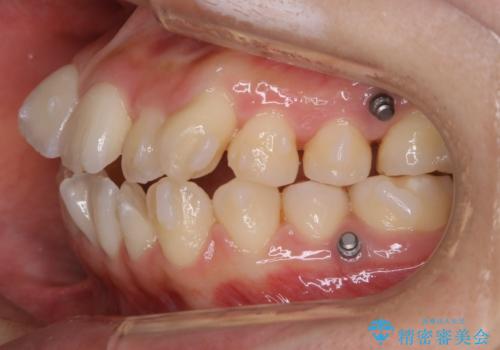

矯正装置の希望がインビザラインだったため、マイクロインプラントを併用し、奥歯から順に遠心移動をかけていくことにより非抜歯でも主訴のガタつきを治すことができました。

マウスピースとマイクロインプラントを組み合わせることで、抜歯をしなくても歯並びを治すためのスペースを作ることができます。奥歯から順に移動させていくので前歯に変化が出るまでには時間がかかりますが、その分健康な歯を抜歯することなく理想的な歯並びを手に入れることができます。